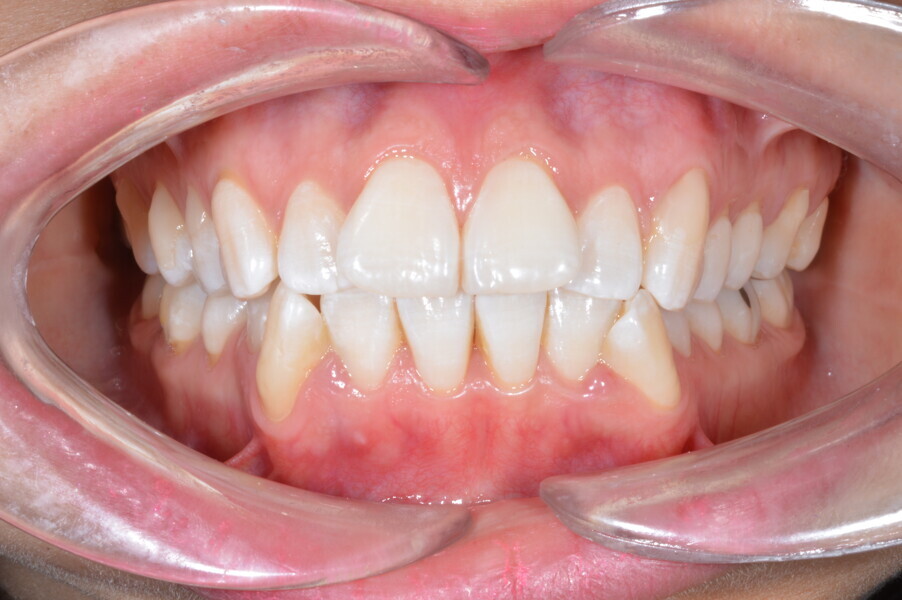

Before the aligner treatment began, the maxillary and mandibular second premolars were extracted to create space. With orthodontic treatment, distalisation of the anterior teeth was achieved by employing maximum mandibular anchorage and moderate maxillary anchorage (Figs. 5–7). At the end of the treatment, a stable bilateral Class I occlusion had been achieved, as well as normal inclination and retrusion of the anterior teeth, consequently improving the profile (Figs. 8–10).

At the end of the treatment, the patient showed a significant improvement in her profile thanks to the orthodontic treatment (Fig. 11) and an improvement in her facial shape thanks to the injection of botulinum toxin into the elevator muscles (Fig. 12). She also had a decrease in bruxism and its symptomatology thanks to the combination of both treatments.